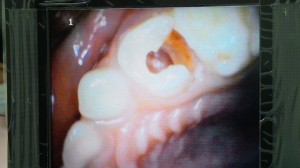

Kerja saya banyak dan tinggalkan terus bawa adik ke dentis.. Alangkah terkejutnya..Bukan saja gigi rosak teruk bernanah sangat banyak bahagian gusi.. dan gigi berlubang sampai 3.. ( patutlah 2 malam menangis dan tak tidur lena ) .. Pesan doktor pada saya ..kanak-kanak x elok cabut gigi usia begini , sebaiknya tampal saja kerana gigi kekal masih lambat lagi akan tumbuh..Saya memang sangat menjaga gigi dan saya mengharapkan anak saya bila besar nanti mempunyai senyuman dan gigi yang cantik …Gigi adalah perkara penting selain muka..Gigi boleh menyebabkan muka tegang..muda dan gigilah menahan kekenduran muka selain kolagen ( Doktor pakar gigi yang bercerita pada saya..) Saya sanggup spend duit demi gigi ,puas hati..!! Wanita lepas bersalin dan berusia gigi makin lemah dan banyak ronggak kerana kurang kalsium , gusi dah tak kuat menampung gigi..